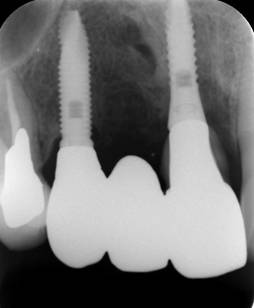

歯周病で抜歯せざるを得ず、インプラントを希望されたケース(使用インプラントはスプライン)

術前。すべての歯が歯周病の末期状態でブリッジ全体がうごいて噛めないとの訴え。右上の犬歯が腫れていました

固定式のブリッジが入っていましたが歯周病で動いています

下顎前歯部には歯石の沈着がみられます

治療後。歯周病で失われた骨が回復しています。使用インプラントはスプラインツイストです。